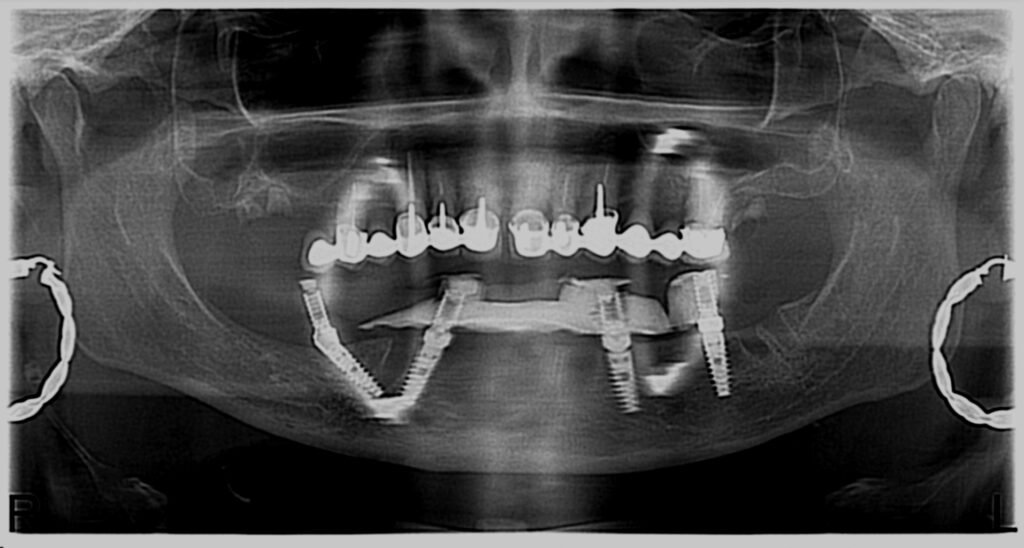

Réhabilitation complète avec mise en charge immédiate (4 implants bas / 6 implants haut)

Le patient se présente avec des dents qui bougent, en haut et en bas.

Nous avons commencé par la mâchoire inférieure avec 4 implants et une mise en charge immédiate.

Trois mois après, le haut a été fait avec le même principe avec 6 implants.

Cette fois-ci, il existait un déficit osseux, résolu par une technique d’expansion sans avoir recours à la greffe d’os.

Les prothèses réalisées sont vissées, ce qui permet de les enlever, les nettoyer une fois par an, ou résoudre n’importe quel problème.